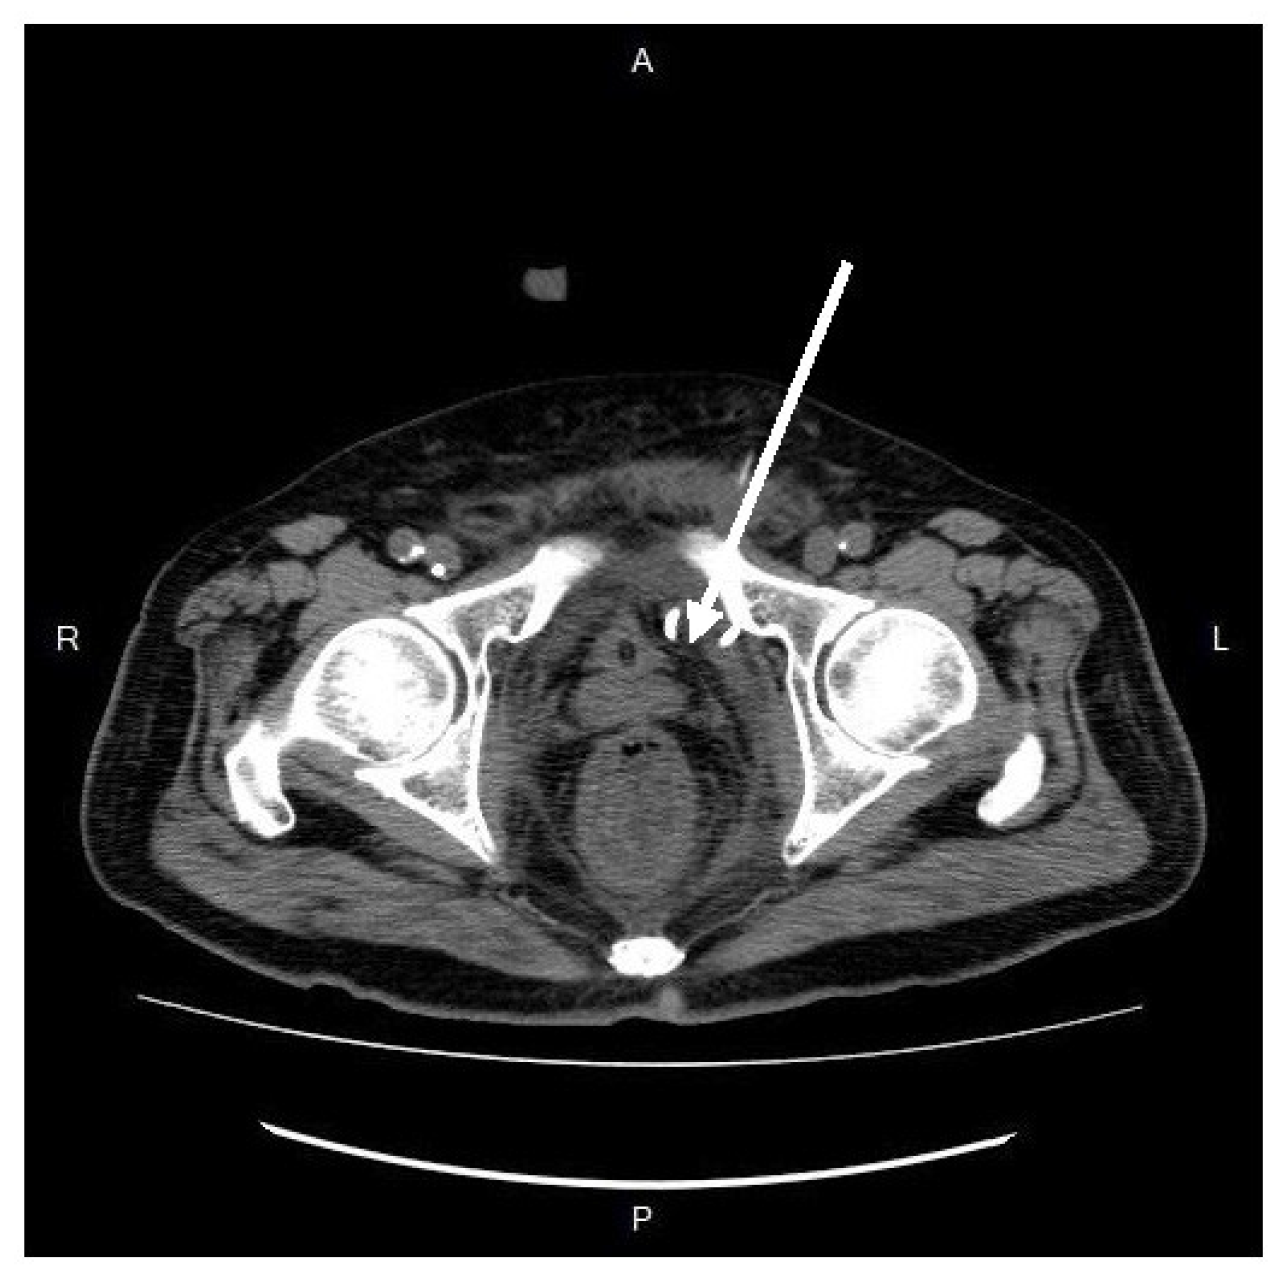

Physical examination revealed pain with deep palpation over the groin and suprapubic area, without rebounding tenderness or signs of deep vein thrombosis in the extremities. The digital rectal examination yielded negative of bloody discharge but noted mild nonspecific pain. The pain did not impact ambulation and normal gait and the strength testing was impaired. The patient did not report dysuria or increased urinary frequency. A plain abdominal radiograph was normal, and laboratory findings consisted of elevated white blood cell count and C-reactive protein (white blood cells, 27,830/μL; neutrophils, 90.6%; C-reactive protein, 21.65 mg/L). Abdominal contrast-enhanced computed tomography (CT) showed a heterogenous fluid-filled perianal abscess, 5.0x4.4x6.8 cm, (Figure 1) in the left perianal region, with extraperitoneal air spreading through the abdominal wall fascia. (Figure 2 and Figure 3)

Figure 1. Frontal view in contrast-enhanced computed tomography. A hypo-attenuated area (size: 5.0*4.4*6.8 cm) on the left side peri-anally, with the air-and-fluid-filled cavity(arrow).